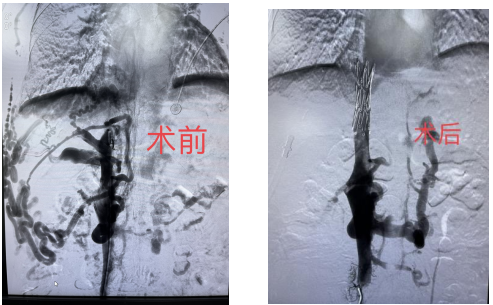

术前术后对比

2022年11月02日08时30分,大竹县人民医院介入科主任孙邱和简阳市人民医院对口支援专家廖懿成功使用介入技术治疗一例布加综合征,切实为患者解除了痛苦。这也是医院首例利用介入手术治疗布加综合征的病例,标志着我院介入技术的进步和医院综合实力的提升。